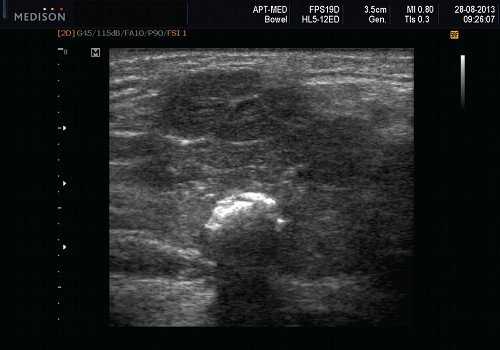

- Необычная кальцификация, наблюдаемая на ультрасонографии при наличии давно существующей опухоли.

- Наличие кальциноза в доброкачественной смешанной опухоли подчелюстной железы указывает на давнюю опухоль и должно вызывать подозрение.

Морфология. Малая плеоморфная аденома: одиночная, цельная, яйцевидная и хорошо разграниченная опухоль. Большая плеоморфная аденома на УЗИ: дольки ± кровоизлияние или некроз ± кальцификация

Серошкальное УЗИ. Хорошо выраженная, солидная и гипоэхогенная по сравнению с прилегающей тканью слюны. Однородная внутренняя эхо-структура с задним акустическим усилением. Опухоль имеет несколько тканевых границ и позволяет звуку легко проникать, вызывая улучшение заднего отдела. Большие опухоли могут иметь неоднородные внутренние эхосигналы из-за кровоизлияния и некроза. Гетерогенная плеоморфная аденома может иметь нечеткие границы, имитирующие злокачественную опухоль. Большие опухоли могут иметь дольки и появляться на ножке. Необычный кальциноз при ультразвуковом сканировании наблюдается при давней опухоли. Кожа и подкожные ткани в норме

Оценивая опухоль слюнной железы, внимательно оценивайте ее характеристики. Край: злокачественные опухоли имеют нечеткие края по сравнению с доброкачественными образованиями. Внутренняя архитектура: злокачественные опухоли имеют неоднородную архитектуру; доброкачественные опухоли обычно имеют однородную архитектуру. Злокачественные опухоли, более вероятно, связаны с внежелезистой инфильтрацией и поражением узлов. Злокачественные опухоли чаще демонстрируют выраженную васкуляризацию с RI> 0,8 и PI> 2,0. Наличие кальциноза в образовании указывает на давнюю опухоль и должно вызывать подозрение на озлокачествление. Важно использовать датчик с высоким разрешением; частота сканирования ≥ 7,5 МГц. МРТ, КТ показаны для больших дольчатых плеоморфных аденом, когда УЗИ не может определить всю анатомическую протяженность. Всегда оценивают как подчелюстные, так и околоушные железы.